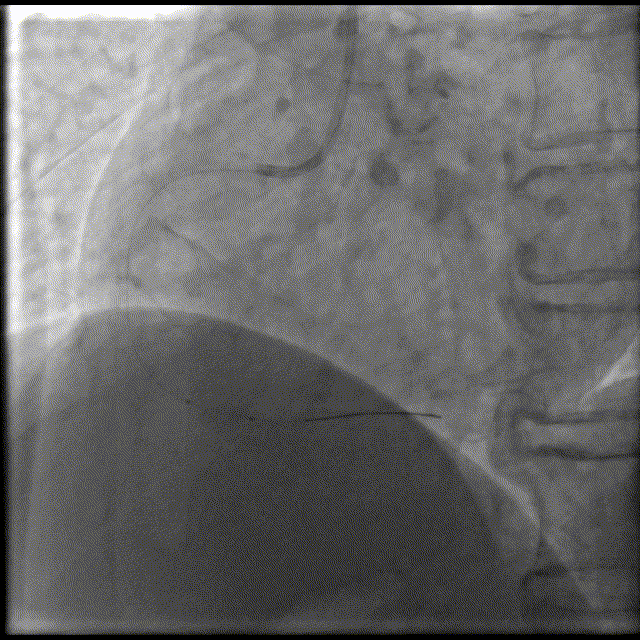

换用6F GC,Telescope™导引延长导管辅助下,2.5x15mm,14-16atm。

Telescope™导引延长导管辅助下,BAT技术,导引延长导管深达第二转折处,2.75x28mm支架顺利到位,12atm释放。

Telescope™导引延长导管辅助下,BAT技术,3.0x15mm,14-16atm后扩张。